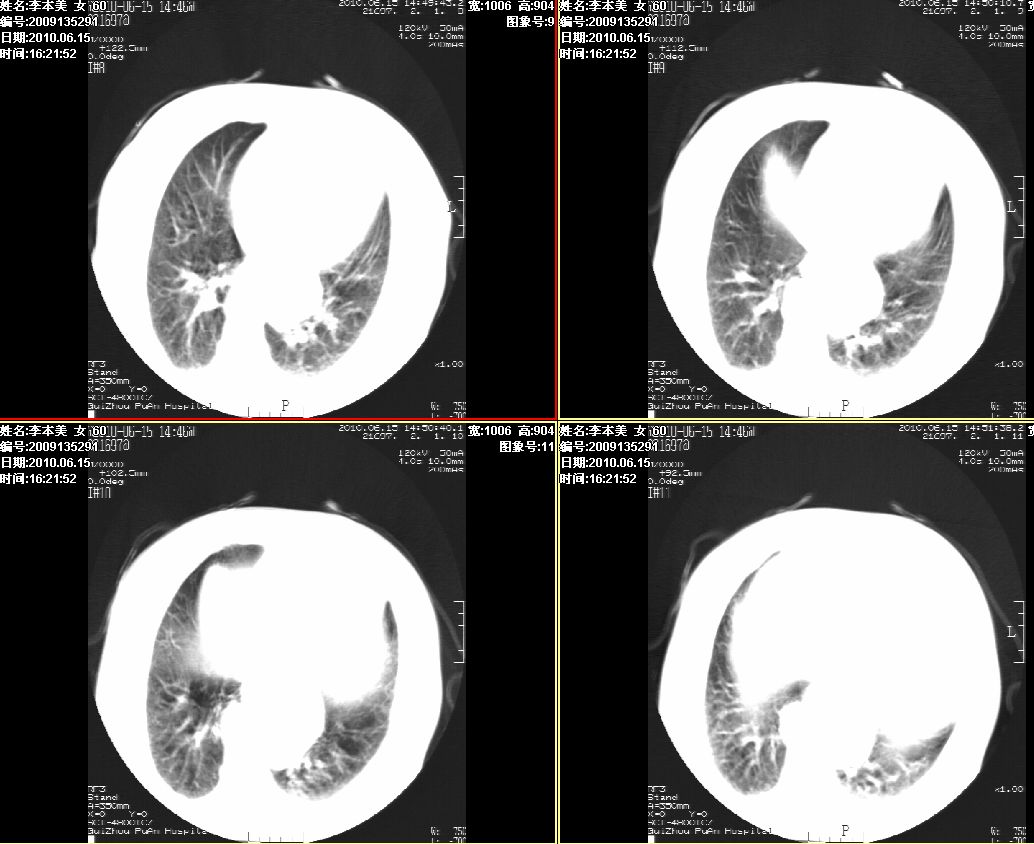

李某,60岁,女,胸闷气促一月,照片发现心后缘圆形高密度影,ct扫描如下。请大家看看,描述一下,给个诊断意见。

降主动脉夹层动脉瘤,建议增扫

占位或夹层动脉瘤,增强扫描

图像欠清,主动脉瘤?食管肿瘤?食管裂孔疝?建议增强。

考虑为:食管裂孔疝; 不排除食道下段肿瘤性病变。

支持夹层动脉瘤,建议cta。

考虑食管裂孔疝, 食管下段肿瘤性病变待排;建议行进一步检查。